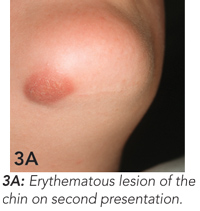

Endodontic treatment was begun, but, because of a dental phobia, the girl delayed completion of this treatment. She presented again 6 months later because the skin lesion had worsened, becoming raised, firm and erythematous (Figure 3A). Endodontic treatment was completed (Figure 3B), and the skin lesion began to heal. At 6-month follow-up, wound contracture had caused dimpling of the skin in the affected area (Figure 3C). This may require surgical revision.